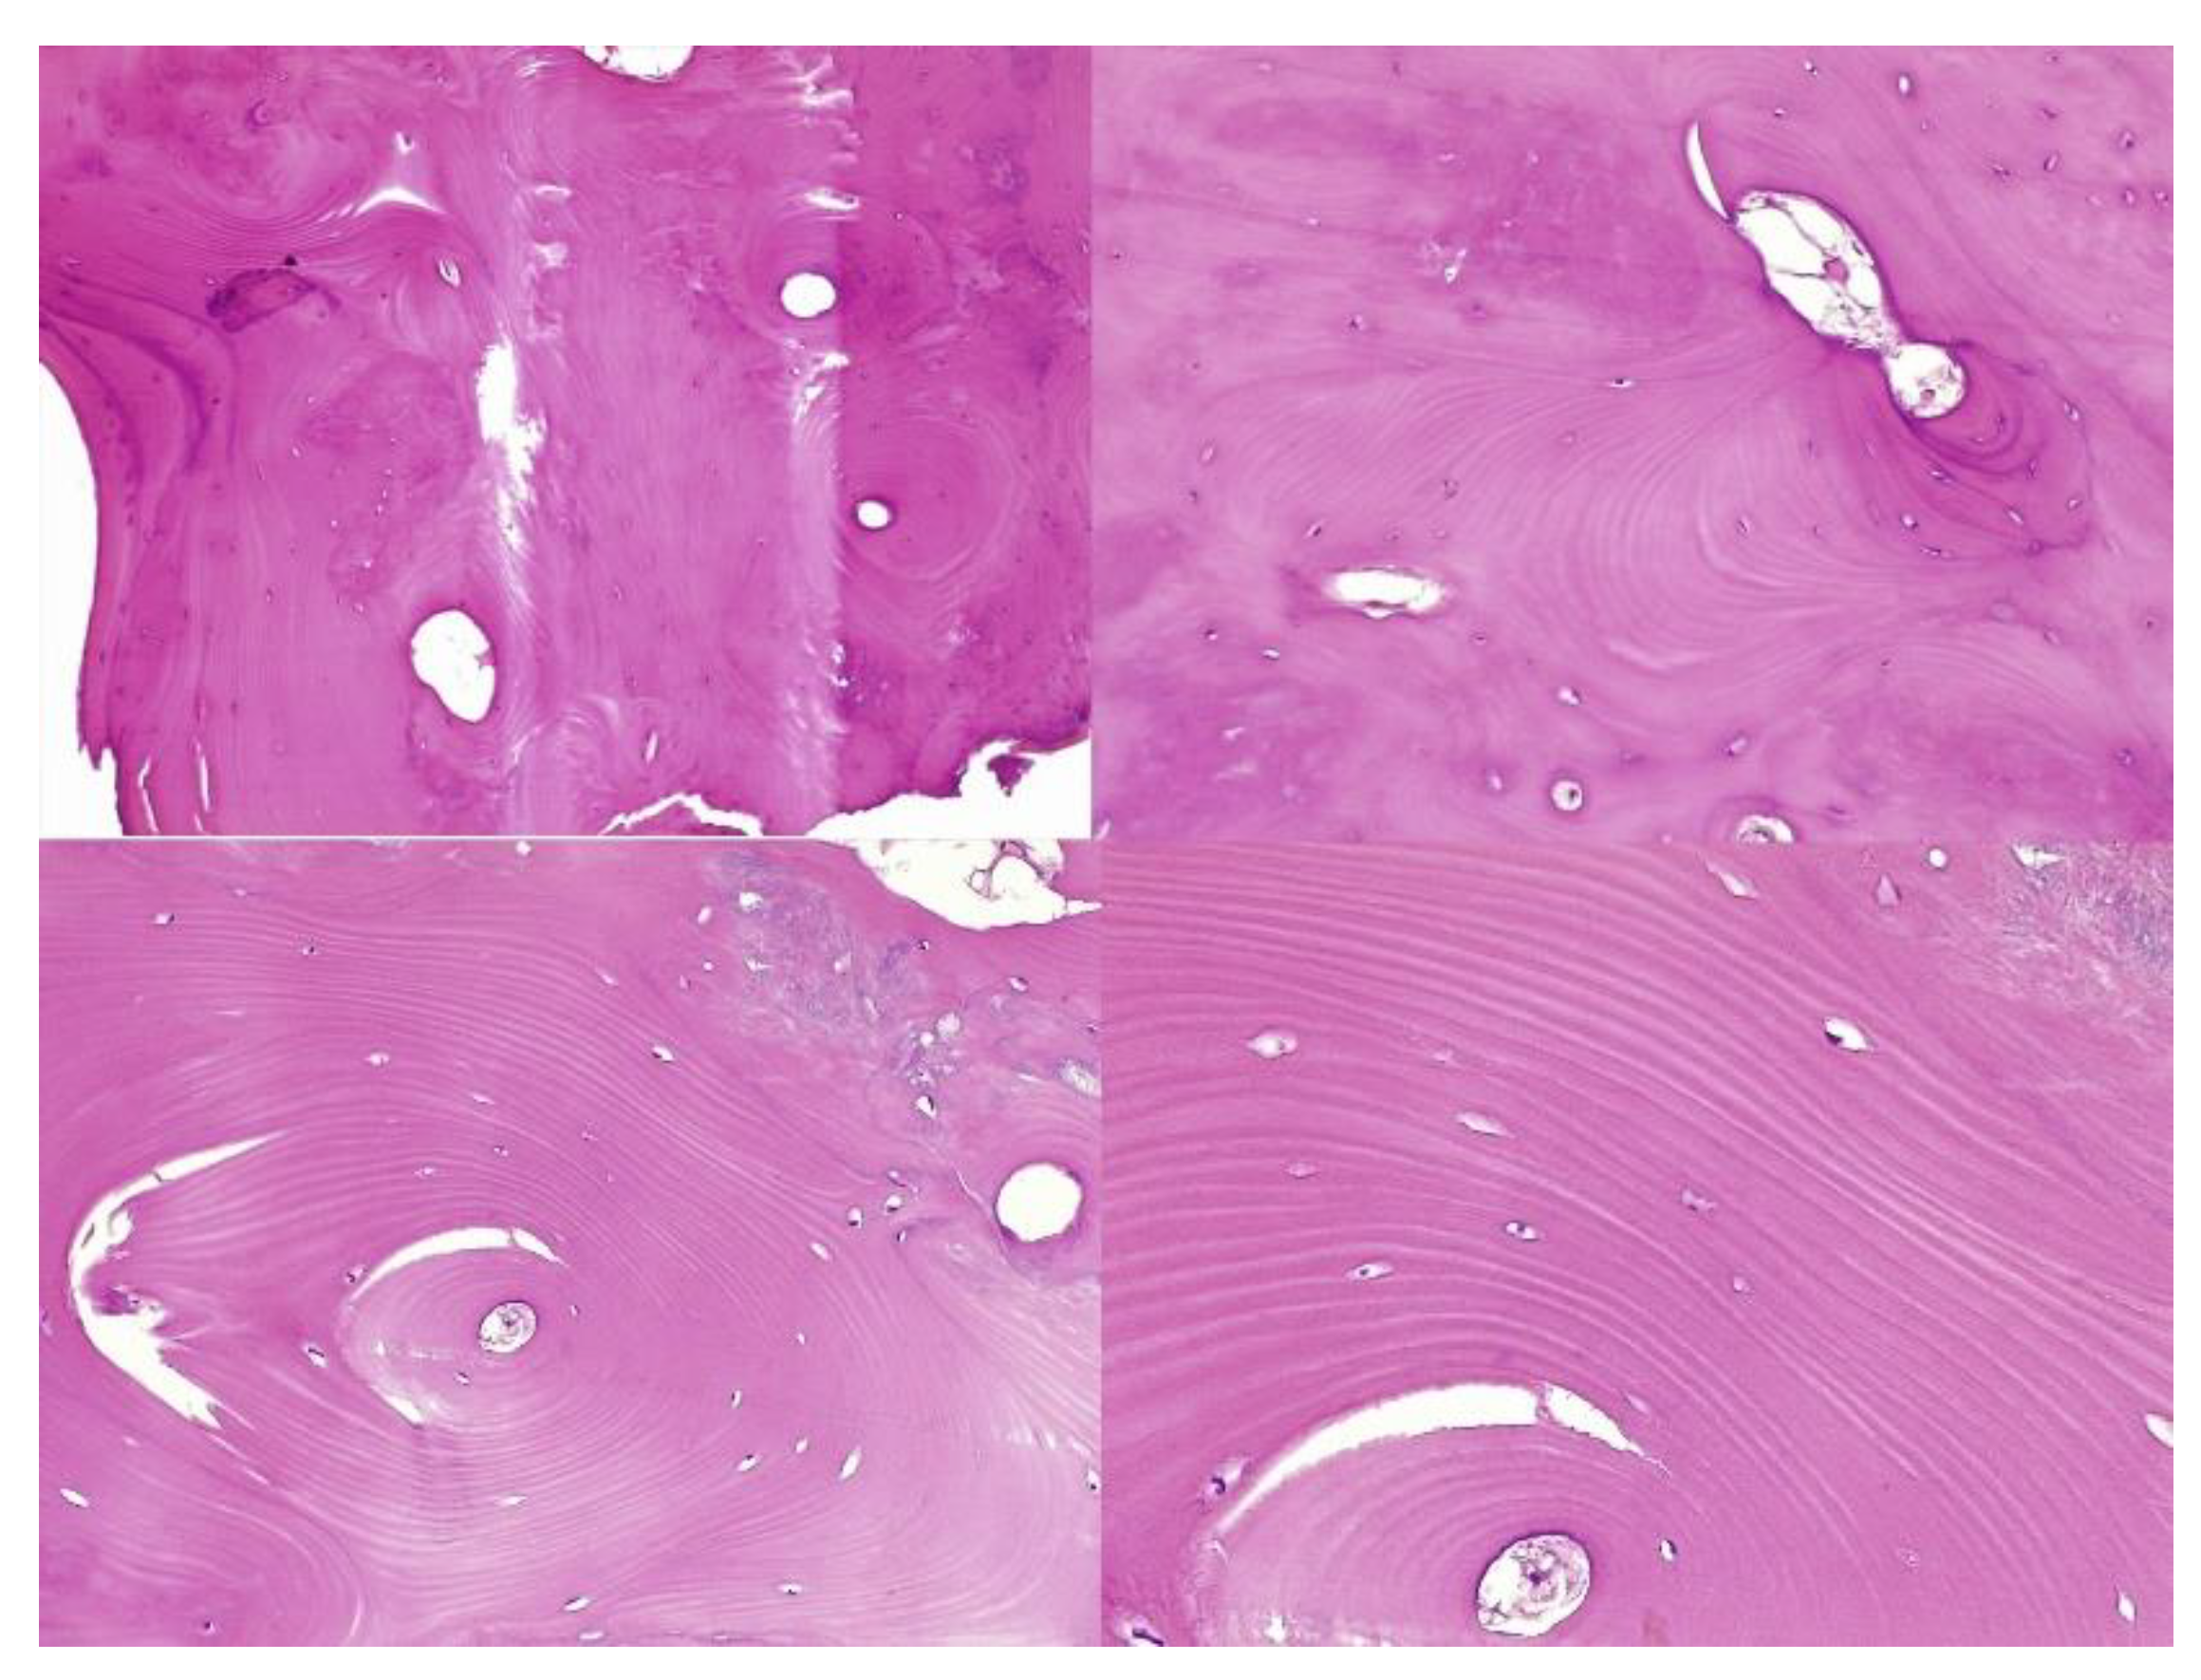

The histopathological result supported the diagnosis of melorheostosis (Figure 5, Figure 6, Figure 7 and Figure 8). Additionally, immunohistochemical tests completed the data obtained after the microscopic examination through the classic histopathological technique. CD45/LCA (clone PD7/26/16 and 2B11, Biocare) demonstrated the presence of inflammatory cells, but overall, the rest of the immunohistochemical tests were non-specific and did not reveal the presence of epithelial or other tumor proliferations on the analyzed specimens. CD138 (clone B-A38, Biocare) showed rare plasma cells dispersed in hematoforming marrow, CD56 (clone BC56C04, Biocare) highlighted few osteoblasts, and all specific immunomarkers for cytokeratins were negative (Pan Cytokeratin AE1/AE3 clone AE1/AE3 and CK8/18 clone CK8/18 both from Biocare). Ki67 (clone SP6, Biocare) was negative in areas of reactive fibrosis and positive in a few cells in the hematoform marrow, suggesting a benign lesion. CD56 usually highlights neuroendocrine tumors, myeloma, myeloid leukemia, and Nk/T cell lymphomas and is also positive in some rare sarcomas. The negative panCK marker denied the possible epithelial tumor origin. Although there are no specific immunomarkers for this pathological entity, there are some studies that try to find correlations between the immunohistochemical expression of some proteins and the severity of the lesions. One study used immunohistochemistry to investigate the expression of several proteins in the affected bone tissues of melorheostosis patients. The study found that there was increased expression of certain proteins, including transforming growth factor beta (TGF-β), bone morphogenetic protein 2 (BMP-2), and insulin-like growth factor 1 (IGF-1) in the bone tissues of melorheostosis patients compared to healthy controls [8].

The histopathological appearance varies, but several pathognomonic changes have been identified, such as increased bone cortical density, the presence of woven bone features, hypervascular features, an increased number of Haversian systems, and irregular bone growth into the medullary cavity; moreover, newly deposited unmineralized osteoids were seen in affected lesions [23].

Figure 7. Remarkably dense compact bone with no significant architectural alteration, consistent with melorheostosis.

Figure 8. The osseous nodule consisted of mildly hypercellular compact lamellar bone with slightly irregular cement lines.